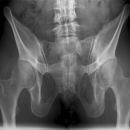

Becken a.p.

>90% aller Beckenringfrakturen lassen sich in der Übersichtsaufnahme, ggf. mit zusätzlicher Inlet und Outlet- Aufnahme (Bestimmung von Richtung und Ausmaß der Dislokation), diagnostizieren;

- Symmetrie des Beckenskeletts, Position der Darmbeinkämme

- Weite und Symmetrie von Symphysenspalt (< 6mm) und ISF (< 4mm)

- Querfortsätze der unteren LWS, Kontur der Sakralforamina, ggf. CT

- Kontinuität der ilioischiadischen und iliopubischen Linie

- Azetabulumfraktur: vorderer und hinterer Pfannenrand, Pfannendachkontur, Köhlersche Tränenfigur, ggf. Zusatzaufnahmen (ap-Zielaufnahme, axiale, Ala- und Obturatoraufnahme), sowie CT

- Schenkelhalswinkel, Weite des Hüftgelenksspalt (4-5mm nach medial, 3-4mm nach kranial)

- Hüftluxation? Hüftkopf in der Beckenübersicht und in der axialen Aufnahme in der Pfanne zentriert?